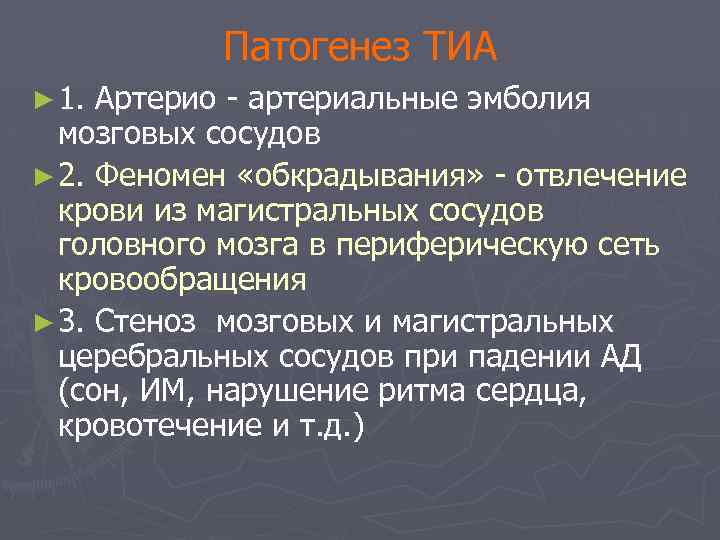

Патогенез ТИА ► 1. Артерио - артериальные эмболия мозговых сосудов ► 2. Феномен «обкрадывания» - отвлечение крови из магистральных сосудов головного мозга в периферическую сеть кровообращения ► 3. Стеноз мозговых и магистральных церебральных сосудов при падении АД (сон, ИМ, нарушение ритма сердца, кровотечение и т. д. )